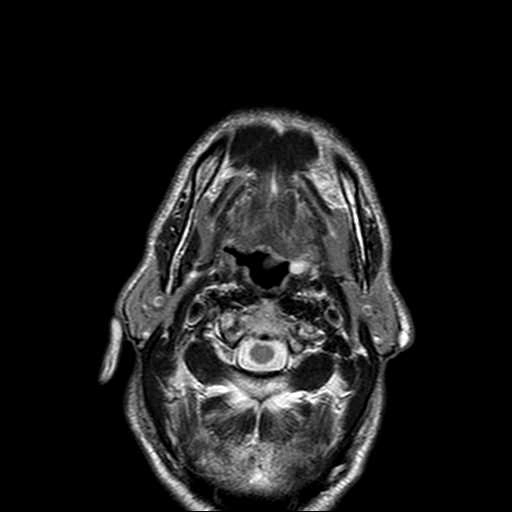

U vỏ bao thần kinh ngoại biên ác tính vùng cổ (Malignant Peripheral Nerve Sheath Tumor of Head and Neck)